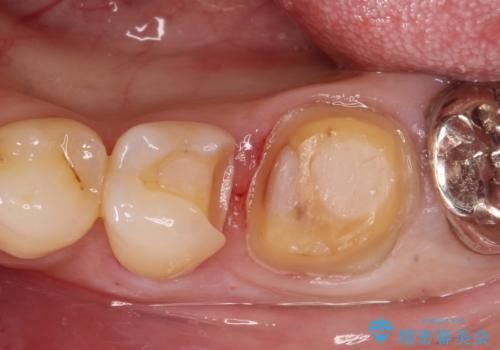

- 金属の詰め物が外れたことを主訴に来院されました。

隣の歯もむし歯を認め、セラミックインレーとセラミッククラウンにて治療を行なっております。